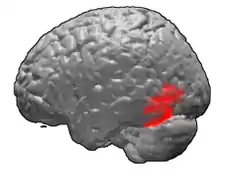

Brodmann area 37

Brodmann area 37, or BA37, is part of the temporal cortex in the human brain. It contains the fusiform gyrus which in turn contains the fusiform face area, an area important for the recognition of faces.

This area is also known as occipitotemporal area 37 (H). It is a subdivision of the cytoarchitecturally defined temporal region of cerebral cortex. It is located primarily in the caudal portions of the fusiform gyrus and inferior temporal gyrus on the mediobasal and lateral surfaces at the caudal extreme of the temporal lobe. Cytoarchitecturally, it is bounded caudally by the peristriate Brodmann area 19, rostrally by the inferior temporal area 20 and middle temporal area 21, and dorsally on the lateral aspect of the hemisphere by the angular area 39 (H) (Brodmann-1909).[1]